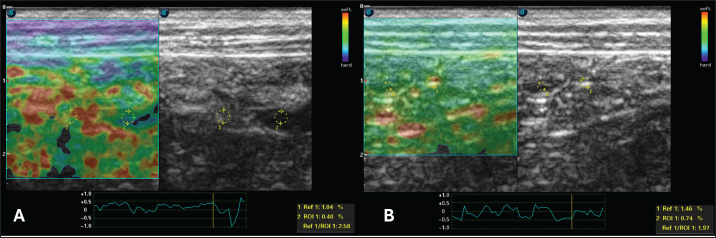

For the static qualitative assessment, the proximal segments of the duodenum and jejunum were analyzed in a longitudinal ultrasound section, and a heterogeneous distribution was found between the dorsal and ventral regions of the intestine, with patterns ranging from predominantly blue with some greenish parts and reddish foci (Fig. 2). To obtain the semiquantitative parameters, the region of interest (ROI) was drawn using the device’s software cursor. Initially, a reference, ROI 1 was obtained in the mesentery adjacent to the intestines, and ROI 2 was drawn in the dorsal region of the duodenum and jejunum. The drawings were similar and circular with the same depth and horizontal direction in the cross-section. The drawings were based on the diameter of the animal’s intestinal mucosa, and the force applied was guided by the elastographic compression wave. The strain ratio (SR) was obtained by calculating the ratio between the ROIs. The values for the duodenum were as follows: ROI 1=1.04 % and ROI=0.4%, with an SR of 2.58 (Fig. 3A). In the jejunum, ROI 1 measured 1.46 %, ROI 0.74 %, and SR 1.97 (Fig. 3B).

Fig. 3. Semiquantitative cross-sectional deformation elastography of the intestine of a dog with intestinal lymphangiectasia. The SR was obtained by evaluating ROI 1 of the mesenteric and ROI 2 of the dorsal region of the intestinal segment. A duodenum with an SR of 2.58 B-Jejunum with an SR of 1.97